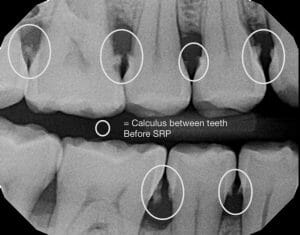

Scaling and Root Planing (SRP), which is commonly referred to as a deep cleaning or gum therapy, is the removal of plaque along with smoothing the roots of your teeth. And when patients who visit our office are diagnosed with gum disease, a deep cleaning is what we’ll recommend.

Some typical signs of gum disease that we most commonly see in the office are swollen and bleeding gums (especially while brushing), calculus near or below your gums, bad breath, and pain in your gums.

Following our assessment, we’ll use a few injections of anesthetic to numb your teeth and gums. Then we will use our water pressure tool to clean out the bacteria before doing our final assessment, and maybe taking some additional X-rays to make sure we’ve removed all of the bacteria.